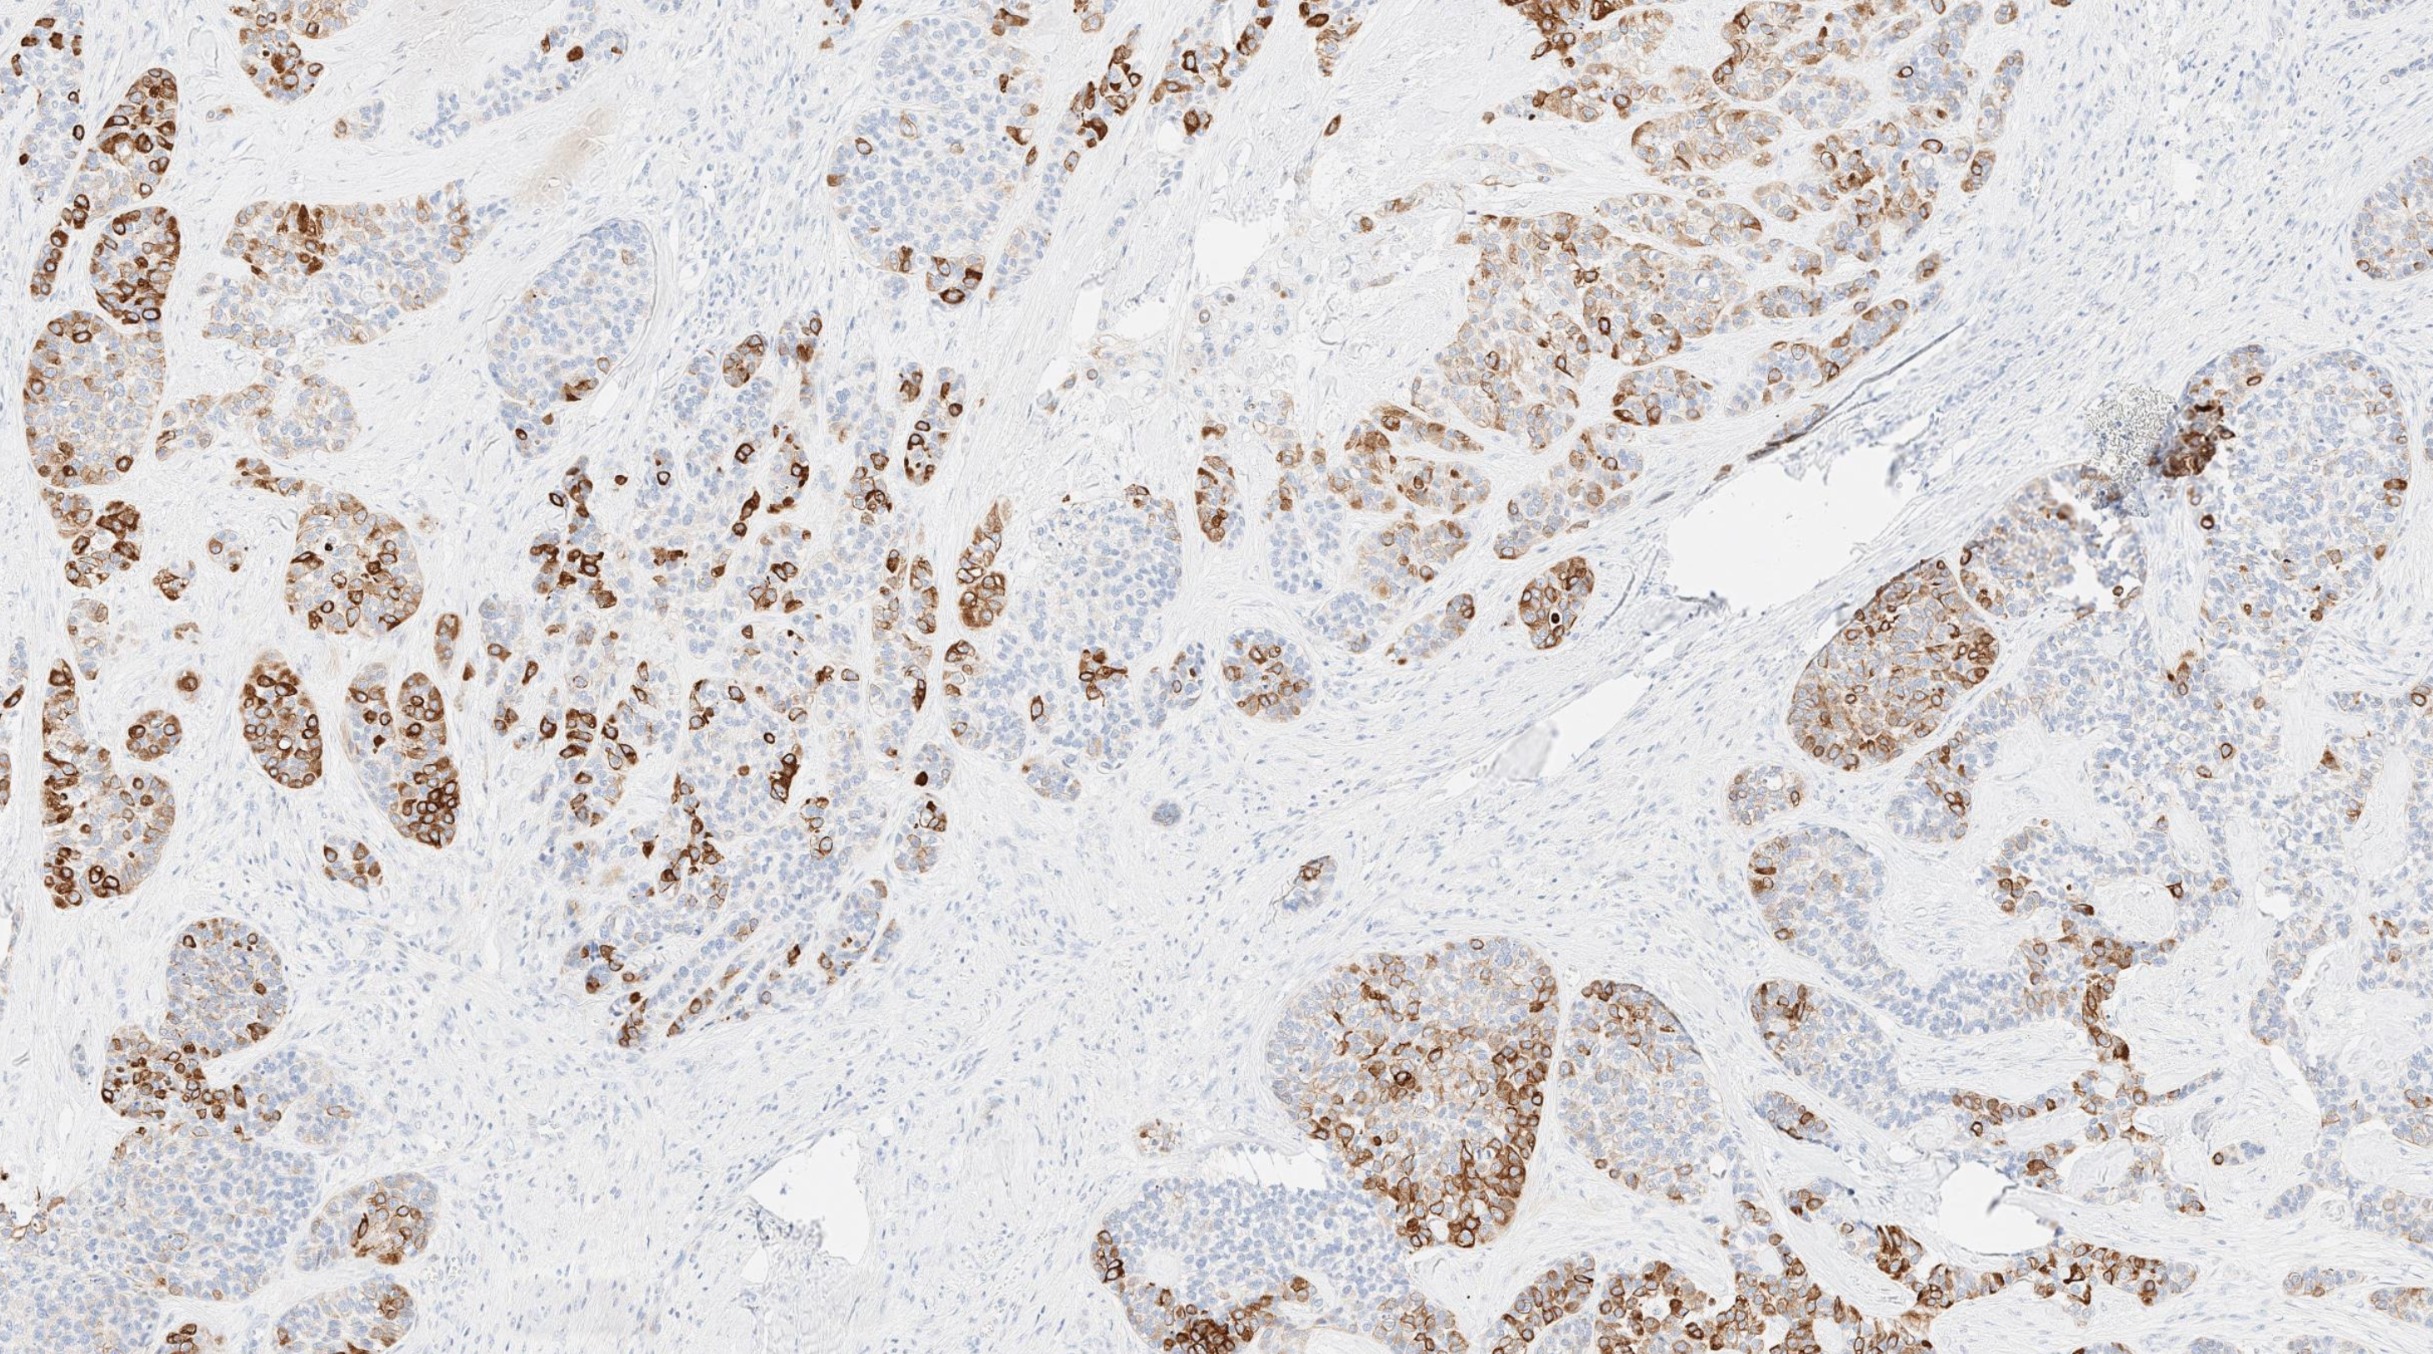

Microscopic (histologic) images

Contributed by Abeer Salama, M.D. and Bin Xu, M.D., Ph.D.

Positive stains

- Comment: The tumor shows a mitotic index of 8 per 10 high power fields. Tumor necrosis is noted. Immunohistochemistry studies show that the tumor is positive for S100, calponin and CAM5.2, whereas negative for HMB45. The morphologic and immunohistochemical features are most consistent with myoepithelial carcinoma.

B. The low power H&E clearly shows invasion, which supports a diagnosis of carcinoma and excludes benign entities, such as pleomorphic adenoma. At high power, the tumor contains one type of tumor cells, which exclude all carcinoma with biphasic patterns (e.g. adenoid cystic carcinoma). The immunohistochemical profile is consistent with myoepithelial phenotype. Therefore, the correct diagnosis is myoepithelial carcinoma.